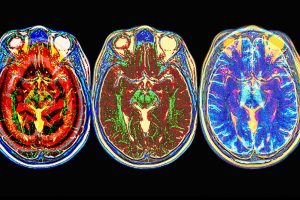

A lo largo de los últimos 20.000 años el cerebro humano se ha reducido aproximadamente […]